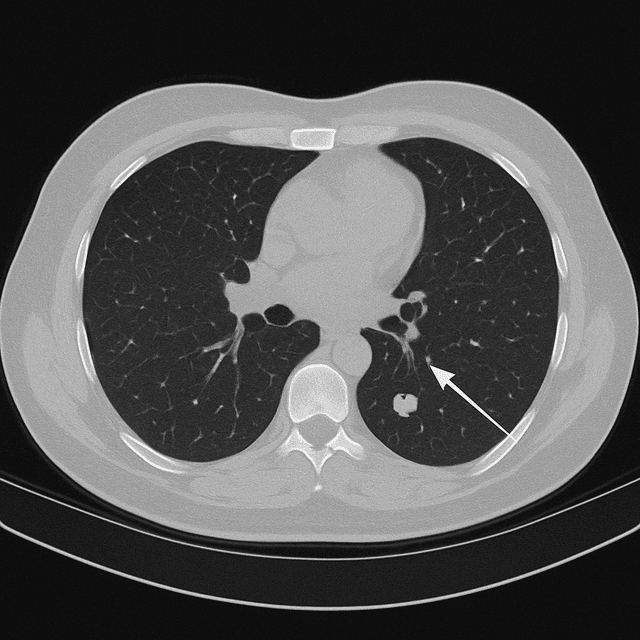

Lung Scan

Screens for early-stage lung cancer and small nodules while they’re still treatable.